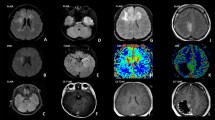

Pathological characteristics of G34-DHGs

Histological features including necrosis, nuclear atypia, mitotic activity and vascular characteristics were assessed. Histopathologic examination of the surgical specimens from our cohort showed high-grade glioma morphology (Fig. 1). All cases showed high cell density, featuring nuclear atypia, mitotic activity and cellular pleomorphism with focal gemistocytic cells and multinuclear giant cells. Most cases were glioblastoma (GBM)-like with microvascular proliferating and/or palisade necrosis and two cases showed focal embryonal appearance. However, calcification, perivascular growth pattern and perineuronal satellitosis, which rarely appears in GBM, were also observed (Fig. 1E, F). All cases showed GFAP expression and negative expression of OLIG2; most cases were negative for ATRX (9/10) and most showed diffuse strong p53 positivity (8/10). The Ki67 labeling index was high, ranging from 20 to 60%. Sanger sequencing revealed that all cases were IDH wild-type and TERT promoter wild-type (Table 1). Methylation PCR revealed that most cases showed MGMT promoter methylation (8/10) (Table 1).

Histological analysis of diffuse hemispheric glioma H3 G34-mutant specimens. Hematoxylin and eosin staining shows embryonal appearance/small cell glioblastoma-like morphology (A), giant cell glioblastoma-like morphology (B), palisade necrosis (C), perivascular growth pattern (D) and calcification (E). F–J Immunohistochemistry for the indicated proteins